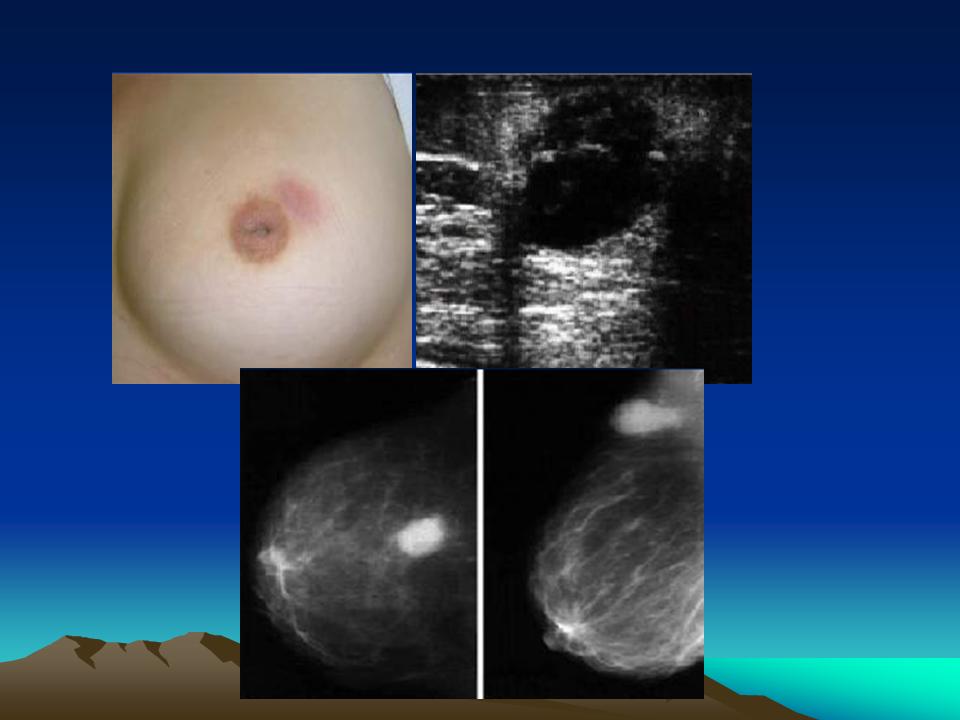

- Lâm sàng: Sưng, đau, sờ thấy mass rõ (giống áp xe vi trùng khác)

- Nhũ ảnh: Vùng tăng đậm độ tròn, bờ không rõ, không có halo sign như fibroadenoma,bệnh nhân lớn tuổi có thể nghĩ đến carcinom.

- Siêu âm: Khối echo kém đường viền rõ có hoại tử trung tâm hoặc khối dạng nang phức tạp, có phù nề mô xung quanh.Bên trong có thể có phản âm kém dạng mô đặc, có tăng sinh mạch máu vào những vùng này.

- Lâm sàng: nhìn da đổi màu,bề mặt da như da cam,có lổ dò,sờ cứng thành mảng, ít di động, ít đau hoặc không đau.

- Nhũ ảnh: tăng đậm độ dạng mô đặc cả một khung, giới hạn không rõ ràng , với da dầy, kèm hạch nách to.

- Siêu âm: những vùng echo kém dạng đặc, diffuse, đường viền rõ, nhưng không có giới hạn thành khối, có phù nề mô xung quanh ở bất kỳ mặt cắt nào, có tăng sinh mạch máu vào vùng echo kém.